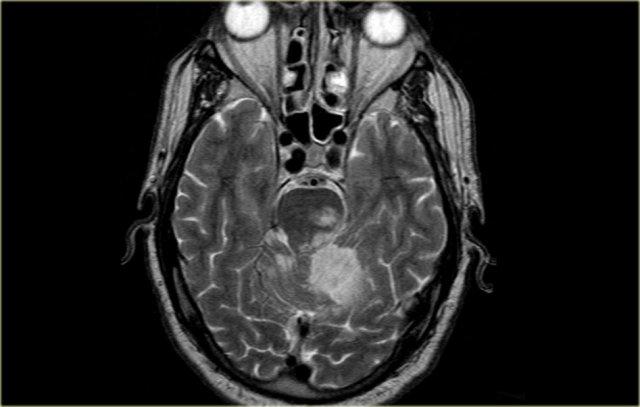

Bên trái là hình ảnh chuỗi xung T2W của bệnh nhân bị nhồi máu trong vùng tưới máu của động mạch não giữa (MCA).

Lưu ý rằng các động mạch xuyên thấu kính – vân bên của MCA cũng bị tổn thương (mũi tên màu cam).